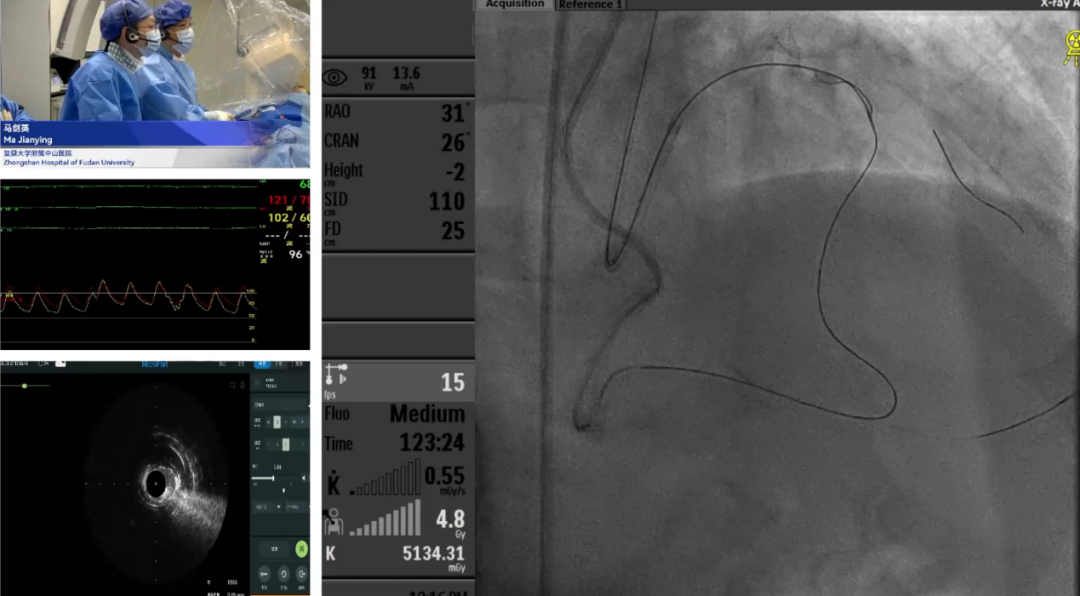

手术1:IVUS指导CTO精准介入

马剑英教授及厦门大学附属心血管病医院手术团队

首先,复旦大学附属中山医院马剑英教授协同厦门大学附属心血管病医院手术团队,展示了一例 IVUS如何指导CTO的开通、真假腔的判别及治疗方案的选择。患者为72岁男性,有长期高血压、吸烟史及十二指肠溃疡出血史,因反复胸痛入院。冠脉造影显示多支血管严重病变,合并LAD CTO。患者此前已完成LCX支架植入,本次手术重点处理LAD CTO。手术首先尝试正向开通LAD,先后通过对角支及间隔支侧支尝试开通,均未通过。随后转为经间隔支侧支成功开通后降支,并进一步通过后降支侧支逆向开通LAD。术中IVUS证实导丝走行路径为“真-假-真”腔,并提示LAD中段存在严重钙化。为充分预处理病变,团队采用旋磨对LAD中段钙化处进行处理,最终使用药物球囊完成LAD治疗。该病例充分体现了IVUS在高阻力复杂CTO病变中精准指导侧支开通、判断导丝位置、确认钙化范围等方面的重要价值,同时也展示了正向、逆向策略灵活转换与腔内影像及治疗技术整合应用在复杂冠脉病变处理中的策略意义。